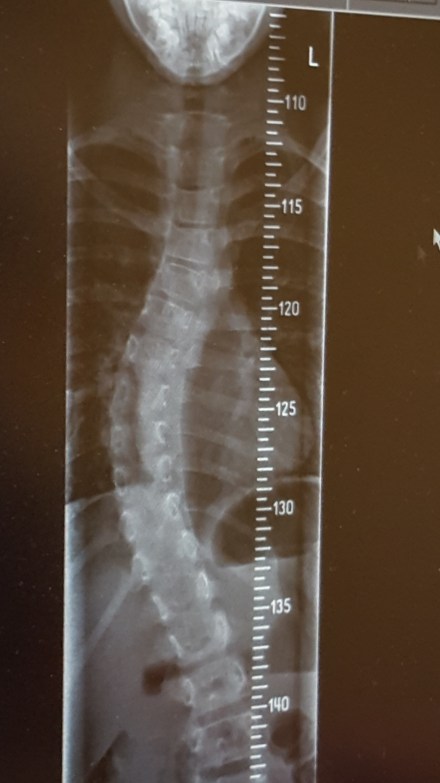

Ik moest vroeger regelmatig via de school dokter naar de diΓ«tiste. Mijn zoon ook sinds hij op de basis school zit. Op een gegeven moment ging hij na elke maaltijd op de weegschaal staan. Toen moest ik stoppen van de arts. Dat was ook mijn idee. Inmiddels loopt mijn dochter al een tijdje in het Wilhelmina kinder ziekenhuis in verband met een scoliose. Een vergroeiing in haar rug.

Zij heeft nu al een tijd een corset om. Sinds januari dag en nacht. En haar rug gaat super hard de goede kant op. Helemaal geweldig natuurlijk. Maar als je eenmaal in een academisch ziekenhuis bent zien ze van alles. Bij Eva via een MRI heeeeeel veeeel. Daarvoor gaan wij nu elke week voor onderzoeken. Tot nu toe valt alles nog mee. Maar haar gewicht…… ze eet als een 4 jarige. Oh oh. Niet best. Gisteren nog eens met de diΓ«tiste gebeld. Wij eten te braaf. Meer slagroom, knakworsten of blokjes kaas mogen op het menu. En ondertussen mogen wij speciale drankjes proberen. Twee per dag. Kijken of dit helpt.